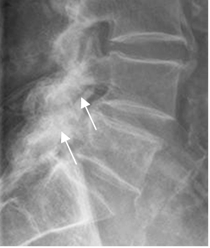

Fig 65. Articulaciones intervertebrales.

Rx lateral. Hipertrofia de facetas articulares, con disminución del espacio y esclerosis.